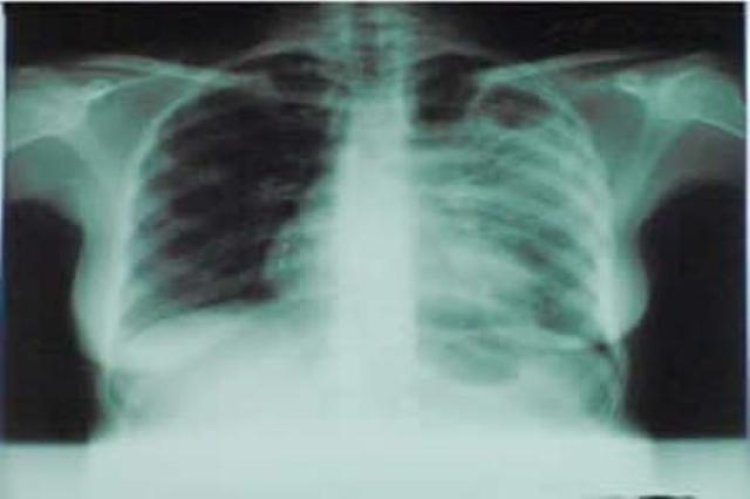

Dr Migambi Patrick umuyobozi ushinzwe ishami ryo kurwanya indwara y'Igituntu mu kigo k’igihugu gishinze ubuzima (RBC) yavuze ko u Rwanda rwakoze ibishoboka kugira ngo imibare y’abandura indwara y'Igituntu igabanuke, gusa ngo haracyari imbogamizi za bamwe mu barwara Igituntu ntibajye kwivuza bigatuma aribo bagira uruhare mu gukwirakwira kw'iyi ndwara.

Yagize ati: “ Abajyanama b'Ubuzima bagize uruhare mu gufasha kugabanya imibare y'abandura iyi ndwara y'Igituntu. Gusa haracyari imbogamizi kuko hari bamwe mu bagira ibyago byo kwandura Igituntu batajya kwivuza, kuko ubushakashatsi bwerekanye ko 60% batajya kwivuza bigatuma iyi ndwara y'Igituntu ikwirakwira mu bantu.”

Dr Tuyishime Albert ushinzwe gukumira no kurwanya indwara mu kigo kigihugu kita kubuzima (RBC), waje uhagarariye Minisitiri w'Ubuzima muri uwo muhango, yavuzeko abanyarwanda bakwiye kwisuzumisha mu gihe bumvise bafite kimwe mu bimenyetso by'indwara y'Igituntu harimo Inkorora, kugira umuriro ukabije n'ibindi, kuko iyo uvuwe hakirikare ukira kandi ntakiguzi bisaba kuko ari ubuntu, ikindi bakumva ko umuntu urwaye igituntu atari amarozi nkuko bamwe babivuga.

Mu myaka 20 ishyize u Rwanda rwagabanyije umubare w'abarwayi ku kigero cya 42%, ni mugihe kandi umubare wa bapfa nawo wagabanutseho 38%

Umwaka ushyize wa 2022 90% barwaye indwara y'Igituntu baravuwe barakira . Ni mugihe 32 batazi indwara y'Igituntu nk’uko ubushakashatsi bwabigaragaje.

Ubusanzwe umurwayi w'igituntu wafashe neza imiti nyuma y'ibyumweru bibiri ntaba acyanduza. Buri mwaka abantu bari hagati 4000- na 5000 nibo bagaragarwaho n'indwara y'Igituntu.